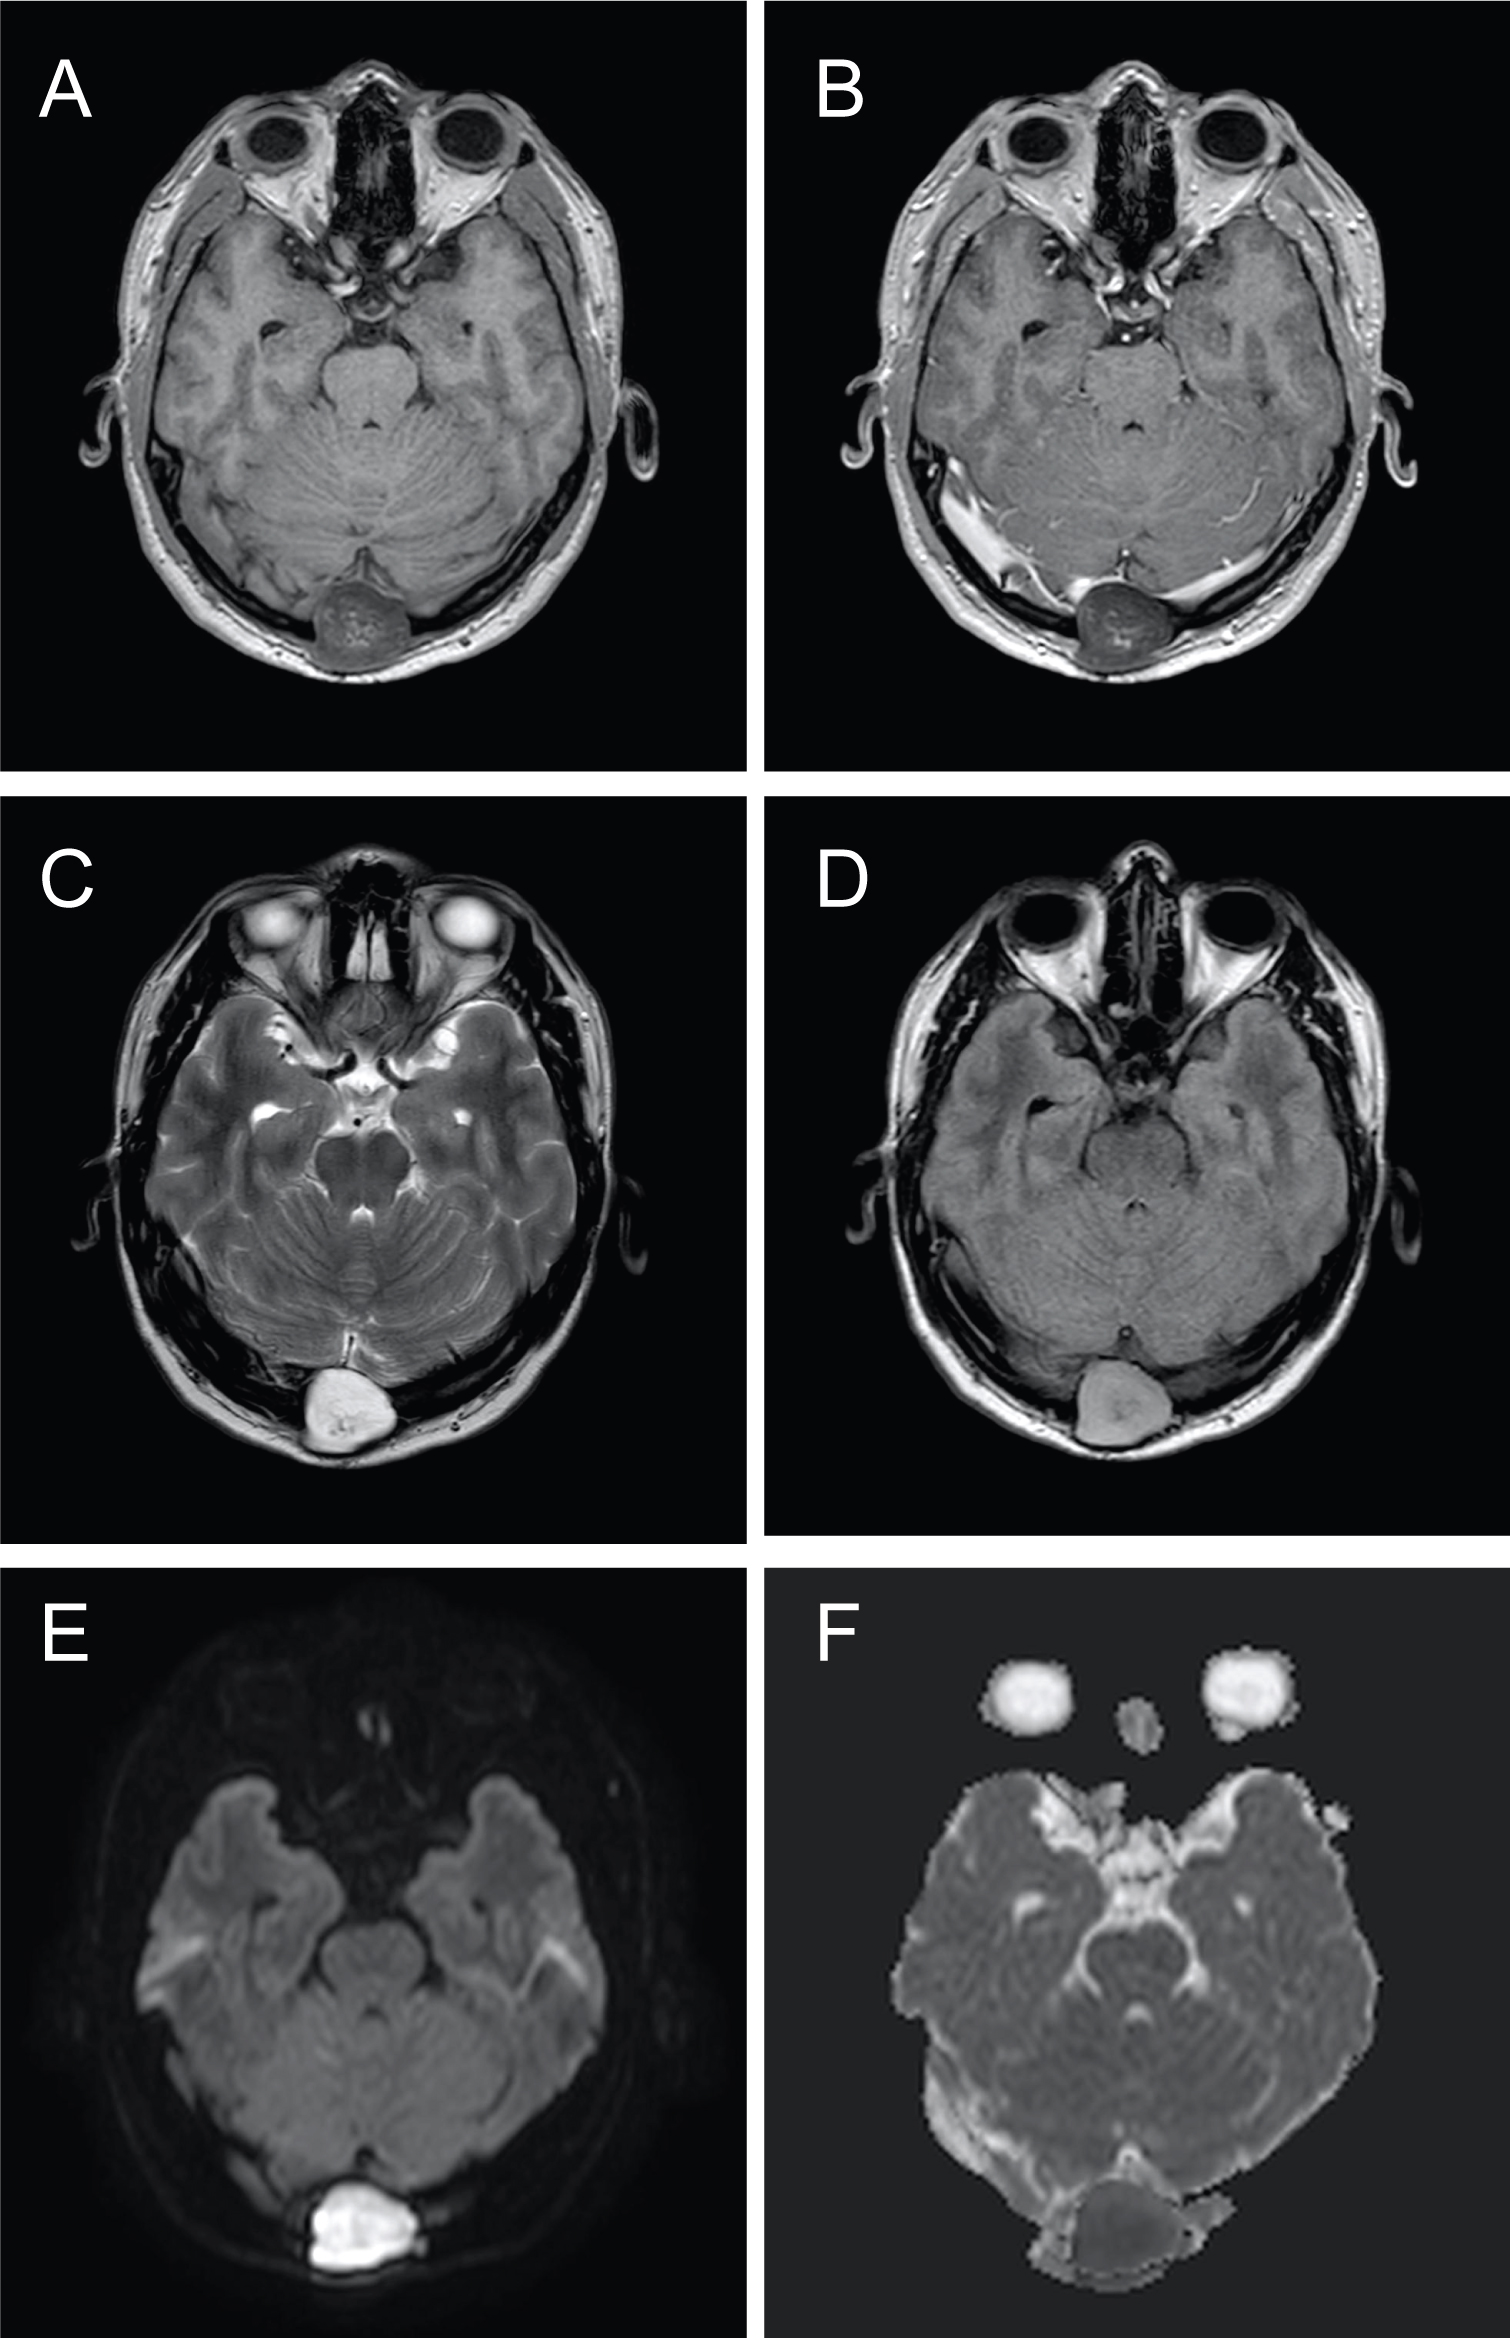

In our case, the patient was an adult, diagnosed with a palpable mass at his occiput, which was proven to be an intraosseous epidermoid cyst, compressing on the confluence of the sinuses, causing increased ICP and visual symptoms and papilloedema. It is advisable for scalp lesions, especially overlying important anatomical structures, to perform brain imaging, before attempting excision (Figure 1, Figure 2, Figure 3 and Figure 4).

Figure 4: Original magnification ×200, haermatoxylin and eosin stain, showing keratin flakes in keeping with the contents of an epidermoid cyst. View Figure 4